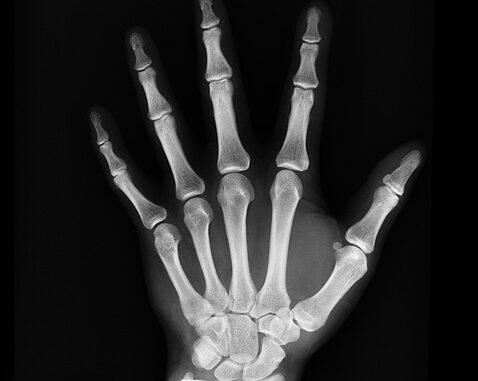

Un equipo de científicos en China ha desarrollado un nuevo pegamento óseo llamado “Bone-02”, inspirado en las ostras. Este pegamento puede reparar huesos rotos en 2-3 minutos sin necesidad de cirugía mayor ni implantes. Funciona en condiciones húmedas y salinas y  las pruebas revelaron que su fuerza de unión es superior a 181 kg y presenta una resistencia al cizallamiento de 0.5 megapascales, así como una resistencia a la compresión de 10 megapascales.

Además, “Bone-02” es biodegradable, lo que significa que se absorbe en el cuerpo a medida que el hueso sana, evitando cirugías adicionales. Este nuevo material podría permitir cirugías menos invasivas y mejorar la curación de fracturas, reduciendo complicaciones y costos.

Si los ensayos clínicos siguen siendo positivos, podría cambiar la cirugía ortopédica al permitir que los huesos sanen naturalmente.